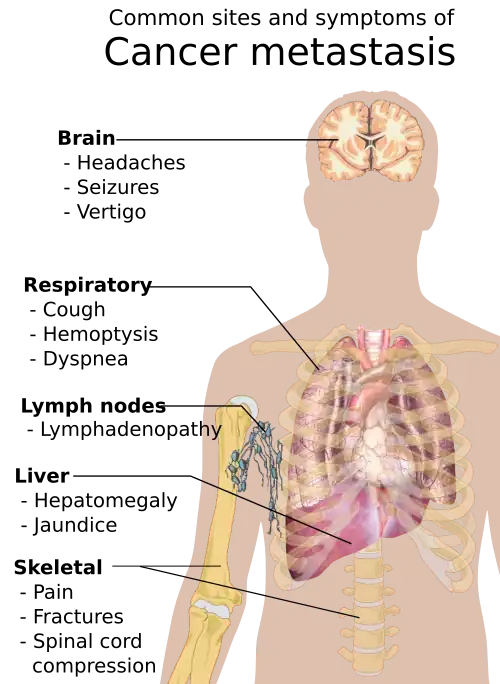

Metastasis is the spread of cancer to other locations in the body. The dispersed tumors are called metastatic tumors, while the original is called the primary tumor. Almost all cancers can metastasize.[39] Most cancer deaths are due to cancer that has metastasized.[40]

Metastasis is common in the late stages of cancer and it can occur via the blood or the lymphatic system or both. The typical steps in metastasis are:

Different types of cancers tend to metastasize to particular organs. Overall, the most common places for metastases to occur are the lungs, liver, brain, and the bones.[39]